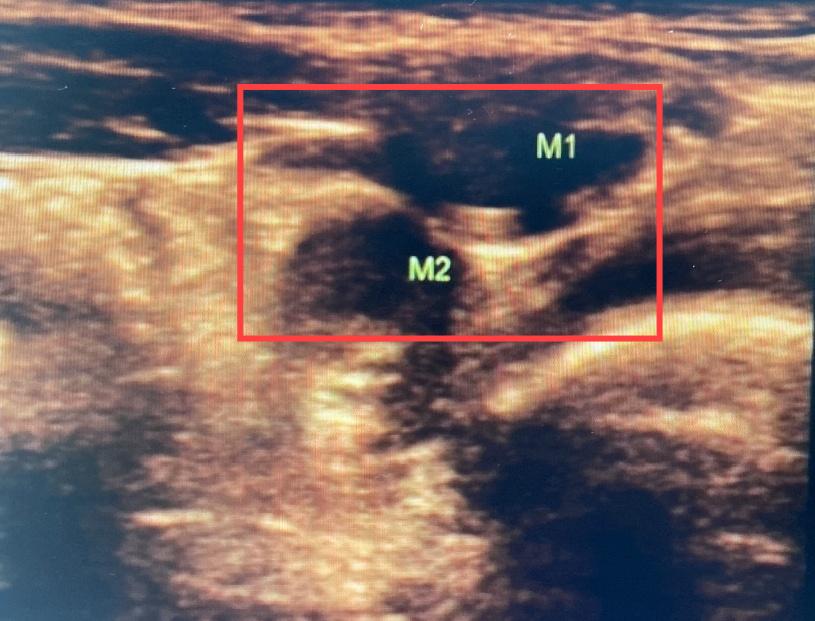

在给小飞进行腹部超声检查后,徐晓龙副主任医师发现小飞右侧的“蛋蛋”极有可能异位到左侧腹股沟内环口处。

入院后,进一步进行盆腔MR扫描,小飞左侧腹股沟区存在两个异常信号影,徐晓龙副主任医师判断小飞左侧隐睾、右侧*丸睾**异位的可能性极大。

MR显示左侧腹股沟区有两个异常信号影